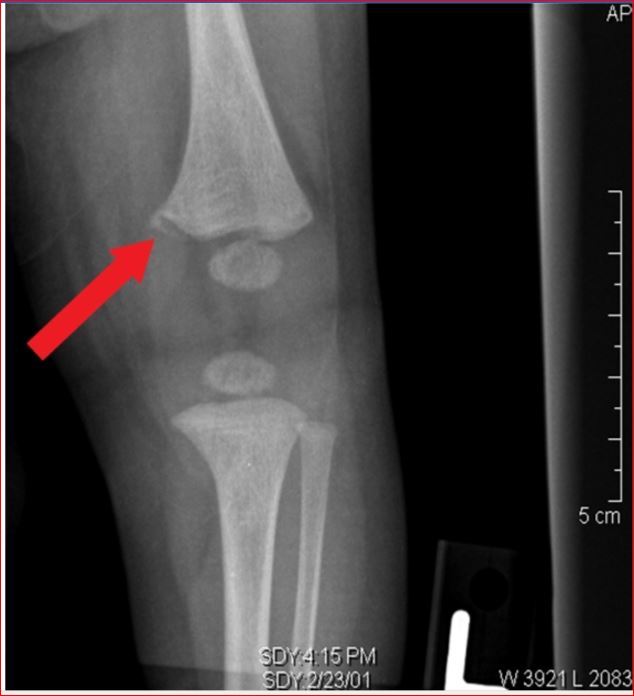

A femur fracture in a nonambulating child

A femur fracture in a nonambulating child, particularly a spiral fracture, is suspicious for a twisting force on the thigh.

WARNING SIGNS OF CHILD ABUSE

Red flags for child abuse include?

Posterior rib fractures,

metaphyseal corner fracture (“bucket-handle”) and

fractures at various stages of healing.